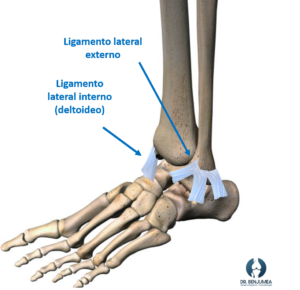

Cómo funcionan los ligamentos del tobillo

El tobillo está sostenido por varios ligamentos. En la parte externa, hay tres ligamentos que forman un triángulo, siendo el ligamento peroneoastragalino anterior el afectado con más frecuencia dado que es el más débil. En la parte interna trabaja el ligamento deltoideo de un grosor considerable, por lo que su lesión aislada es menos frecuente.

El tobillo se encuentra sujetado fundamentalmente por estos ligamentos, y cuando existe una lesión de alguno de ellos, además del dolor y la incapacidad para andar, puede desarrollarse una inestabilidad a largo plazo.

El ligamento lesionado con más frecuencia es el ligamento lateral externo en su fascículo anterior (ligamento peroneoastragalino anterior). Esta lesión se produce por un mecanismo de inversión forzada (el tobillo se mete para adentro), y es típica en tras una caída o una mala pisada donde se produce la torcedura de tobillo.